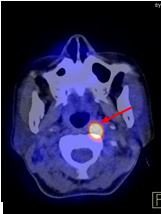

Hình 1 mô tả kết quả ghi hình PET/CT của bệnh nhân Nguyễn Th. B., nữ, 52 tuổi. Gần đây thấy xuất hiện hạch cổ hai bên. Bệnh nhân đi khám và được nội soi vòm mũi họng thì không phát hiện thấy bất thường. X-quang, siêu âm đều cho hình ảnh bình thường. Sinh thiết hạch cổ có kết quả mô bệnh học là ung thư biểu mô không biệt hóa di căn hạch. Vì vậy bệnh nhân được chỉ định chụp PET/CT để phát hiện ung thư nguyên phát. Kết quả chụp PET/CT chỉ thấy hình ảnh ung thư vòm trái, di căn hạch cổ hai bên (tổn thương u vòm nằm dưới niêm mạc thành vòm trái nên không phát hiện được khi nội soi vòm).

Hình 1: Hình ảnh tổn thương nằm dưới niêm mạc thành vòm trái tăng hấp thu FDG mạnh (mũi tên đỏ). Nhiều hạch cổ hai bên tăng hấp thu FDG (mũi tên vàng). Kết luận: Hình ảnh ung thư vòm di căn hạch cổ hai bên.